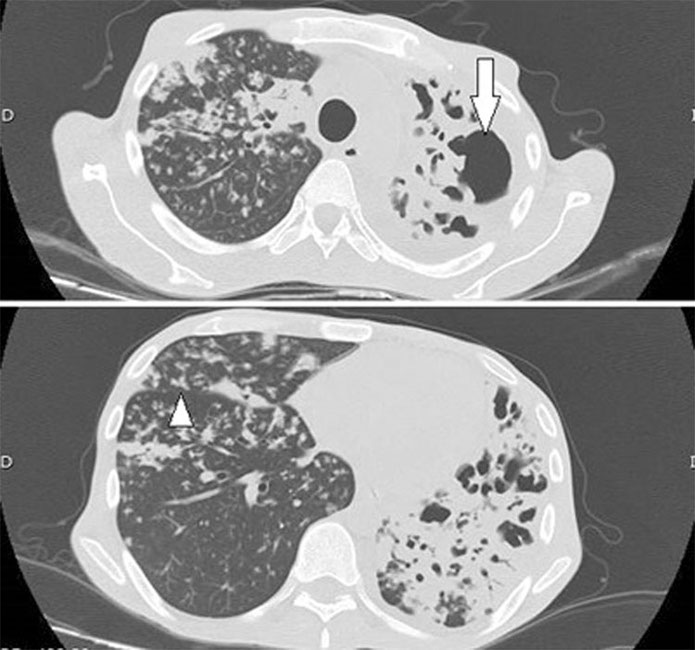

Las cavitaciones tuberculosas ocurren más comúnmente en áreas de consolidación e indican muy sugerentemente que se encuentra una infección activa, son a menudo múltiples y de paredes irregulares y gruesas (Figs. 10, 11 y 12).15,16,17 Es extraño encontrar niveles hidroaéreos, pero cuando se hallan, sugieren la posibilidad de una sobreinfección (Fig. 10).18,19

Hombre de 32 años, con antecedentes de TBC pulmonar, con reactivación de su cuadro, se solicitó TC de tórax, donde se destacó: pulmón izquierdo disminuido de volumen con severa distorsión de la arquitectura pulmonar, con bronquiectasias varicosas y un mínimo remanente de parénquima normal en el lóbulo inferior izquierdo, se aprecian cavitaciones de distintos tamaños (flecha). En el pulmón derecho persisten imágenes de "árbol en brote" (triángulo), asociado a opacidades pulmonares y focos de condensación. Derrame pleural laminar a izquierda.

Hombre de 51 años, con antecedentes de un empiema por TBC complicada. Se solicitó TC de tórax que destacó: en relación al lobo inferior izquierdo se apreció gran cavitación con fístula broncopulmonar comunicante, paredes engrosadas en relación a bronquiectasias periféricas e imágenes hiperdensas cicatriciales. Se observaron opacidades nodulillares centrilobulares con prominentes infiltrados peribronquiales tipo "árbol en brote."

El curso natural de la enfermedad progresa a compromiso lobar y opacidades pulmonares casi completas, asociado a destrucción parenquimatosa (Fig. 11), se produce la llamada enfermedad fibroproliferativa, con engrosamientos reticulares y nodulares.17

La diseminación endobronquial es la complicación más común causante de las cavitaciones tuberculosas, que representan una infección granulomatosa crónica en la cual los organismos activos extienden una necrosis caseosa de las paredes bronquiales (Figs. 10 y 11).17 Los hallazgos en TC se manifiestan como opacidades pequeñas y mal definidas, nodulillares centrilobulares sugiriendo la apariencia de un “árbol en brote” (Figs. 10, 11 y 12).20,21